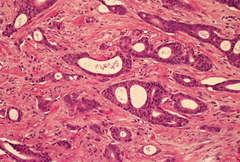

Gastric Carcinoma

Malignant adenocarcinoma of surface epithelial cells sub classified as intestinal or diffuse Intestinal - large, irregular ulcer - lesser curvature - risk factors: intestinal metaplasia (chronic gastritis, nitrosamines (smoked foods), smoking Diffuse - signet rings cells that infiltrate stomach wall --> desmoplasia (thickening/leathery = linitis plastica) - NO risk factor associations Presentation: - presents late --> poor prognosis - weight loss - abdominal pain - anemia - early satiety Early spread (lymph nodes) or liver (portal) - virchow: left supraclavicular - krukenberg: bilateral ovaries, mucin-secreting signet ring cells (diffuse-type) - sister mary joseph: subQ periumbilical